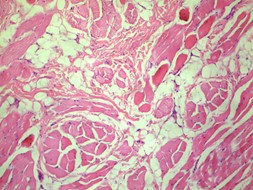

Histopathology of the specimen was notable for abundant haphazard bundles of mature striated muscle admixed with adipose tissue, sclerotic collagen bundles, nerve bundles, and prominent folliculosebaceous adnexa within the reticular dermis and subcutaneous tissue (Figures 1, 2). There was no evidence of cystic elements or malignancy on histopathologic evaluation. Thus, the histopathologic findings were consistent with a diagnosis of RMH.

Figure 2(a,b): Proliferation of well differentiated skeletal muscle within the dermal and subcutaneous layers can be appreciated at high power fields (100x).